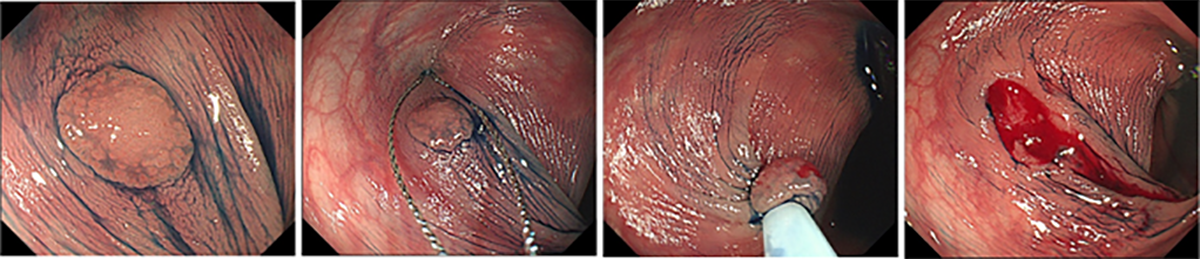

がんになる前の大腸ポリープを内視鏡で取ることで、将来的に大腸がんにかかることを予防できるといわれています。当院では、がんになる前の小さなポリープは、外来での内視鏡検査の際に積極的に取り除いています。これらの小さなポリープに対してはコールドスネアポリペクトミーと呼ばれる方法を主に用いています(図1)。コールドスネアポリペクトミーはスネアを用いて電気を流さずにポリープを切除する方法で、出血や穿孔のリスクが比較的低いとされており安全性に配慮して実施しています。

また、比較的大きなポリープや早期がんに対しては、短期入院のうえで内視鏡治療を行っています。一般的には、投げ輪状の電気メス(スネア)を用いて切除する内視鏡的粘膜切除術(EMR)が行われており(図2)、近年では病変を水中に浮かせて切除するUnderwater EMRも選択されるようになっています(図3)。